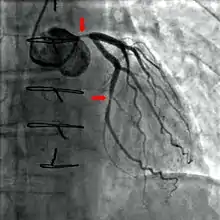

Coronary catheterization is one of the several cardiology diagnostic tests and procedures. Specifically, through the injection of a liquid radiocontrast agent and illumination with X-rays, [1] angiocardiography allows the recognition of occlusion, stenosis, restenosis, thrombosis or aneurysmal enlargement of the coronary artery lumens; heart chamber size; heart muscle contraction performance; and some aspects of heart valve function. Important internal heart and lung blood pressures, not measurable from outside the body, can be accurately measured during the test. The relevant problems that the test deals with most commonly occur as a result of advanced atherosclerosis – atheroma activity within the wall of the coronary arteries. Less frequently, valvular, heart muscle, or arrhythmia issues are the primary focus of the test.

During coronary catheterization (often referred to as a cath by physicians), blood pressures are recorded and fluoroscopy (X-ray motion picture) shadow-grams of the blood inside the coronary arteries are recorded. In order to create the X-ray pictures, a physician guides a small tube-like device called a catheter, typically ~2.0 mm (6-French) in diameter, through the large arteries of the body until the tip is just within the opening of one of the coronary arteries. By design, the catheter is smaller than the lumen of the artery it is placed in; internal (intra-arterial) blood pressures are monitored through the catheter to verify that the catheter does not block blood flow (as indicated by "dampening" of the blood pressure).

The catheter is itself designed to be radiodense for visibility and it allows a clear, watery, blood compatible radiocontrast agent, commonly called an X-ray dye, to be selectively injected and mixed with the blood flowing within the artery. Typically 3–8 cc of the radiocontrast agent is injected for each image to make the blood flow visible for about 3–5 seconds as the radiocontrast agent is rapidly washed away into the coronary capillaries and then coronary veins. Without the X-ray dye injection, the blood and surrounding heart tissues appear, on X-ray, as only a mildly-shape-changing, otherwise uniform water density mass; no details of the blood and internal organ structure are discernible. The radiocontrast within the blood allows visualization of the blood flow within the arteries or heart chambers, depending on where it is injected.

If atheroma, or clots, are protruding into the lumen, producing narrowing, the narrowing may be seen instead as increased haziness within the X-ray shadow images of the blood/dye column within that portion of the artery; this is as compared to adjacent, presumed healthier, less stenotic areas.